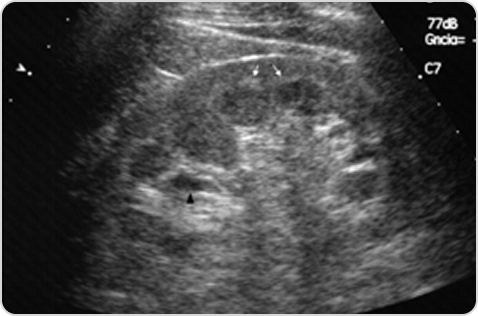

Фабри ауруы кезіндегі бүйректің ультрадыбыстық кескініФабри ауруы кезіндегі бүйректің ультрадыбыстық кескіні

2-сурет. Құрсақ қуысының УДЗ-сы: Фабри ауруы бар пациенттің сол жақ бүйрегінің қыртысты-милық гиперэхогенділігі және парапельвикалық кисталары бар қиғаш кесіндісі.

Дереккөзден бейімделген: Azancot MA, Vila J, Domínguez C, Serres X, Espinel E. Multiple parapelvic cysts in Fabry disease. Nefrología. 2016;36(5):533–536. Open Access.31

Фабри ауруы бар пациенттердің 50 %-ында бүйрек синусының кисталары немесе парапельвикалық кисталар болады32